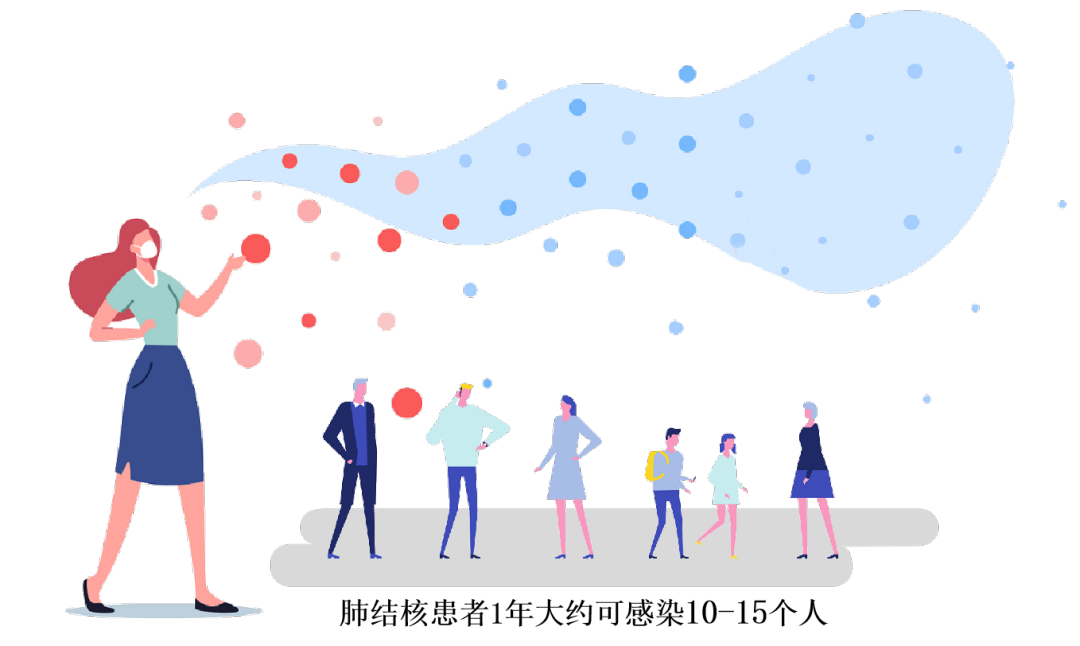

з»“ж ёз—…еҜ№е…¬дј—еә·еҒҘзҡ„еҚұе®іиҝҗеҠЁжҖ§иӮәз»“ж ёжӮЈиҖ…еңЁе’іе—ҪгҖҒжү“е–·еҡҸгҖҒиҜӯиЁҖж—¶�пјҢ�пјҢпјҢдјҡжҠҠеёҰжңүз»“ж ёиҸҢзҡ„йЈһжІ«ж’ӯж•ЈеҲ°з©әж°”дёӯ�пјҢ�пјҢпјҢе‘ЁеӣҙдәәзҫӨеҗёе…ҘеёҰиҸҢйЈһжІ«еҚіеҸҜиғҪеҸ—еҲ°зҶҸжҹ“�гҖӮгҖӮе‘јеҗёйҒ“ж’’ж’ӯж–№жі•еӨ§еӨ§еўһж·»дәҶеҚҙж ёз—…зҡ„зҶҸжҹ“еҚұе®і�гҖӮгҖӮдёҚжІ»з–—зҡ„иҝҗеҠЁжҖ§иӮәз»“ж ёжӮЈиҖ…�пјҢ�пјҢпјҢ1е№ҙзәҰиҺ«еҸҜзҶҸжҹ“10-15е°ҸжҲ‘з§Ғ家�гҖӮгҖӮ